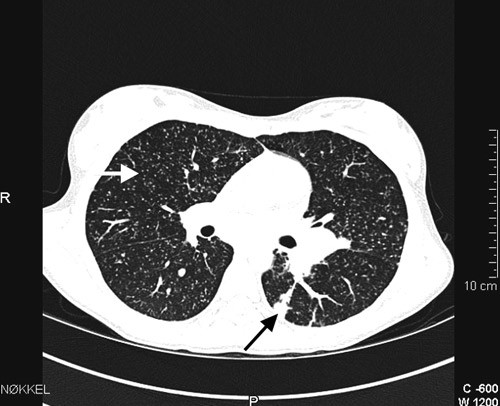

Ved innkomst var det normal respirasjon og normale auskultasjonsfunn over lungene. Det var ingen lymfeknutesvulst. Ho var palpasjonsøm i nedre høgre kvadrant av abdomen. Temperaturen var 38,3 °C. CRP var 49 mg/l og senkingsreaksjonen 25 mm/t (< 10 mm/t). Dei andre blodprøvane var normale. Kalprotektin i avføring var 30 mg/kg (0 – 50 mg/kg). Røntgen av thorax viste sparsomme retikulonodulære fortettingar i båe lunger (fig 1). Spirometri viste nedsett lungefunksjon med restriktivt preg og nedsett diffusjonskapasitet (tab 1). Det vart så gjort høgoppløysings-CT av thorax som viste multiple små noduli med tilfeldig distribusjon i båe lunger, konsolidering i venstre underlapp og forstørra lymfeknutar i mediastinum og hilus (fig 2). MR av abdomen utan kontrast viste normale forhold.

Vi mistenkte på dette tidspunktet pneumonitt eller annan interstitiell lungesjukdom. Retikulonodulære fortettingar i lungene med tilfeldig distribusjon samt mediastinal lymfadenopati gav mistanke om hematogen spreiing av virus, sopp eller tuberkulose. Sarkoidose og immunologiske tilstandar med lungeaffeksjon var også aktuelle differensialdiagnosar sjølv om ein ved sarkoidose oftast vil sjå ein meir peribronkial og perivaskulær distribusjon av noduli.

Vi sendte CT-bilete til Rikshospitalet for vurdering. Immunoglobuliner og revmatologiske prøvar var normale. Det vart påvist IgG-antistoff og IgG-EBNA-antistoff mot Epstein-Barr-virus, men ikkje IgM-antistoff. Ho hadde også IgG-antistoff mot cytomegalovirus. Det vart ikkje påvist antistoff mot Mycoplasma pneumoniae, Chlamydia pneumoniae, Borrelia burgdorferi eller Aspergillus fumigatus. Angiotensinkonverterande enzym i serum var på 69 U/l (9 – 85 U/l). Lymfocyttkvantitering viste noko reduserte nivå av T-hjelpeceller (CD4) og naturlege drepeceller (CD16/56). Vi fekk så melding frå Rikshospitalet om at CT-bileta mest sannsynleg viste miliær tuberkulose. Mantoux-test vart dagen etter avlese til 13 mm (< 6 mm).